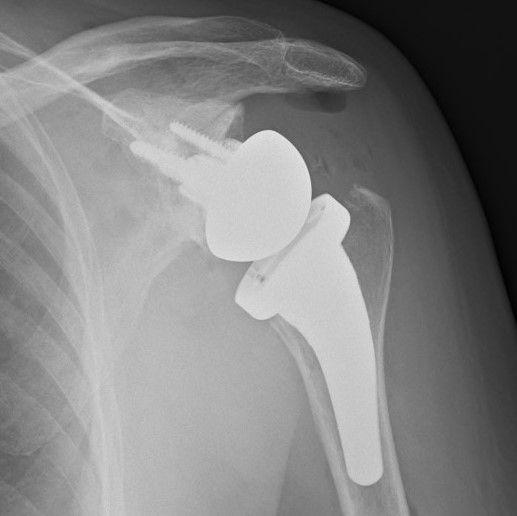

Post operative x ray of a reverse polarity shoulder replacement